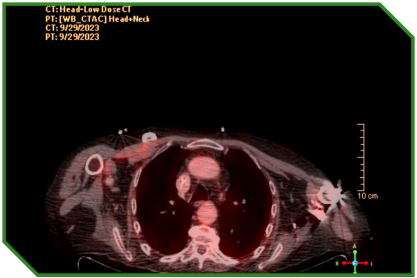

Paciente masculino de 72 anos, portador de carcinoma espinocelular de língua, tratado inicialmente com cirurgia e radioquimioterapia adjuvante, evoluindo com progressão linfonodal e pulmonar. Diante de comorbidades cardiovasculares e fragilidade clínica, recebeu quimioterapia paliativa, seguida da introdução de imunoterapia isolada, após confirmação de expressão tumoral de PD‑L1, permanecendo em acompanhamento clínico e radiológico após suspensão do tratamento por toxicidade imunomediada grave.